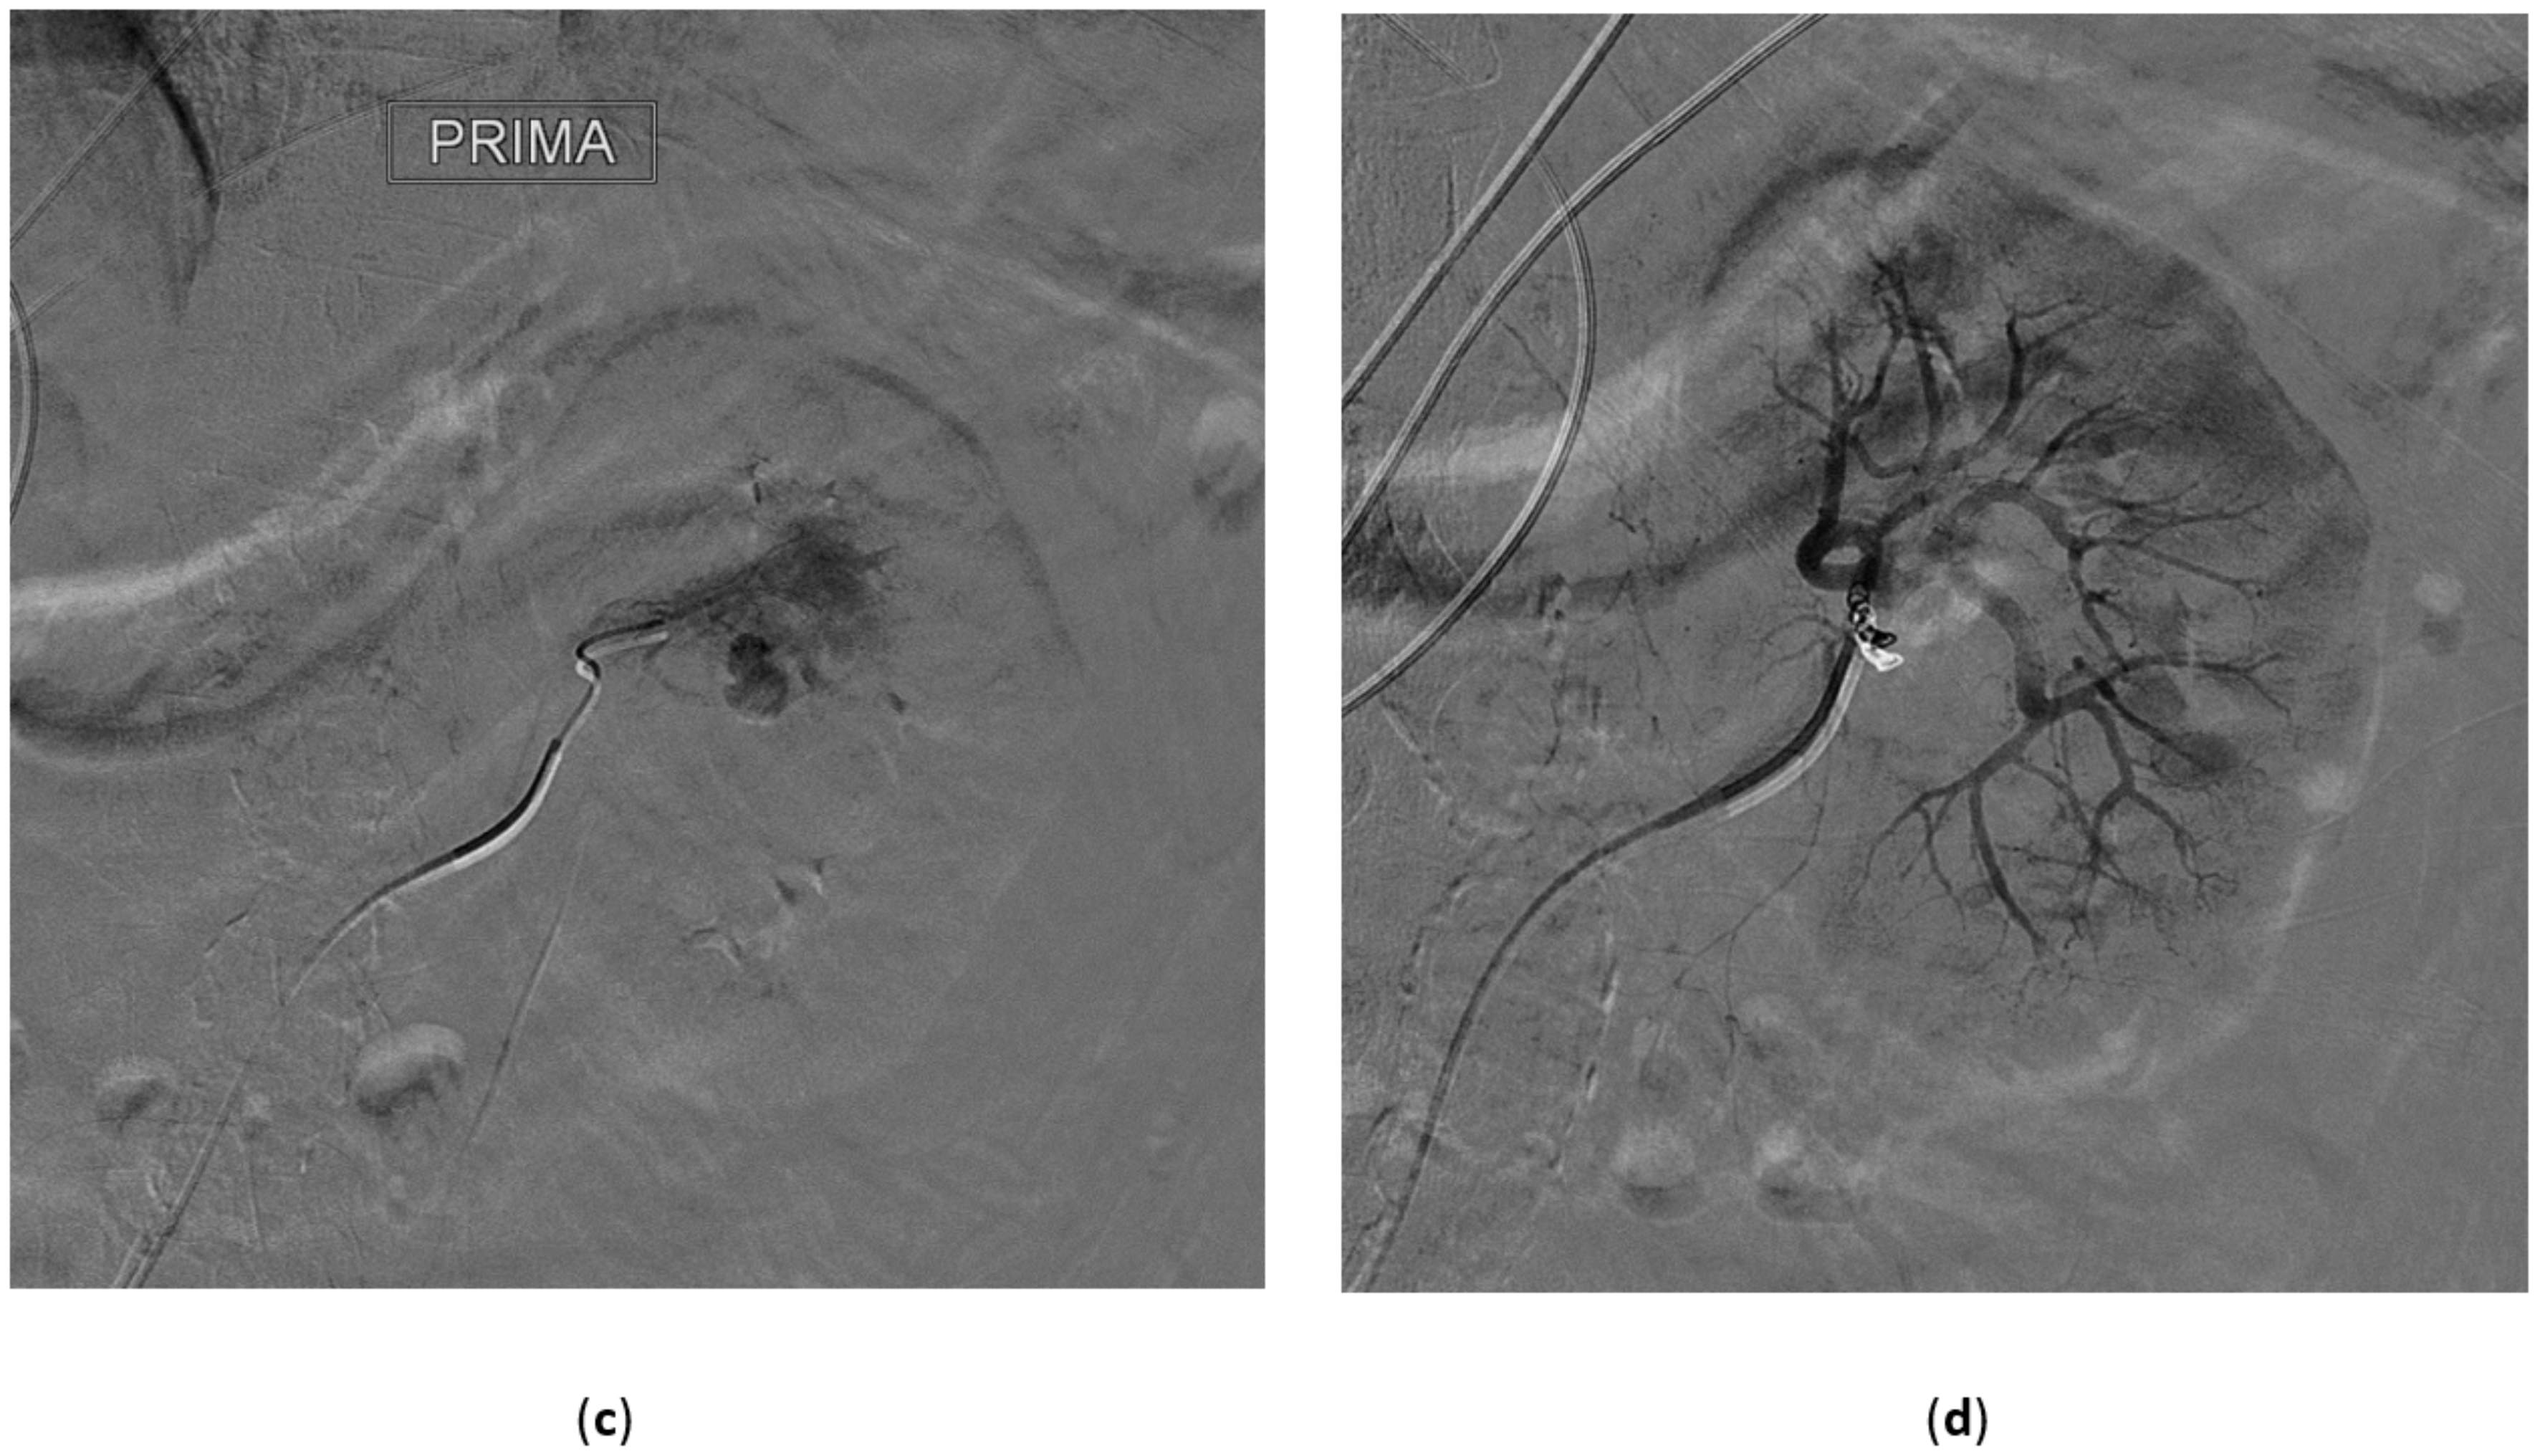

5.1. High-Flow Priapism

5.2. Clinical, Laboratory, and Imaging Findings

5.3. Treatment of High-Flow Priapism